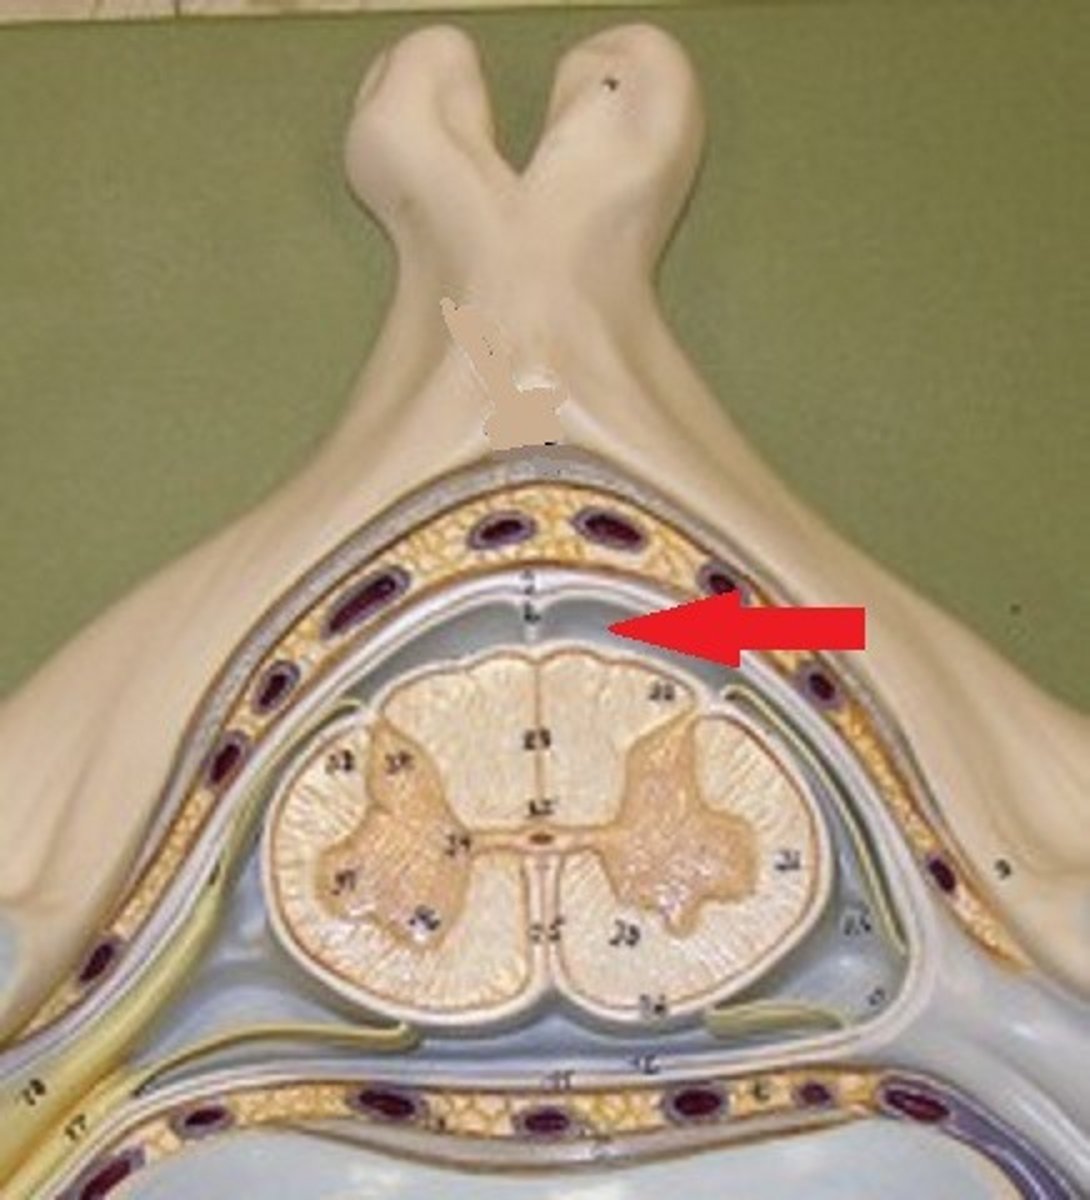

epidural space

dura mater

subdural space

arachnoid mater

subarachnoid space

pia mater

denticulate ligaments